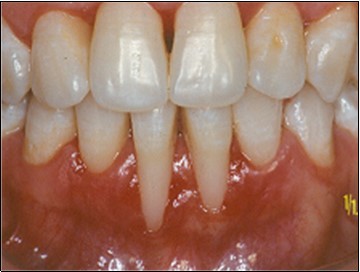

The use of the subepithelial connective tissue graft offers a combination of both the pedicle flap and the free gingival graft. The pedicle flap allows for possible root coverage since it retains its apical blood supply and therefore survives over an avascular root surface5. The free gingival graft supplies a resilient type of connective tissue with a genetic predisposition which ensures thickness and keratinization (Karring and Löe4. The double-blood supply, that from the underlying periosteum and the overlying flap, seems to be enough to nourish the entire graft5. Regarding the effect of the Er:YAG laser for periodontal treatment, its has been advocated because of its potential to decontaminate the diseased root surface and the periodontal pocket7. It may also help to remove the adjacent pocket epithelium and the calculus from root surfaces6,3. Cobbe et al2 and Ando et al1, examined in vivo bactericidal effect and conclude that the exposure of the root surface to laser could significantly decrease the levels of subgingival Actinobacillus actinomycetemcomitans, Porphyromonas gingivalis and Prevotella intermedia. In this study the Er:YAG laser was applied at powers ranging from 25 to 100 mJ/ pulse / sec. The laser irradiation was performed under water irrigation, with the tip held perpendicular to the exposed root to promote decontamination of root surface and try to remove the smear layer produced by instrumentation. The laser was also applied on the free gingival graft to remove keratinized epithelium from connective tissue graft. Those procedures seem to be efficient, although histology is not available at this time. However ours clinical results after 2 years have maintained a stable position (Figure 8).

Figure 8.Postoperative after 2 years.

Postoperative after 2 years.